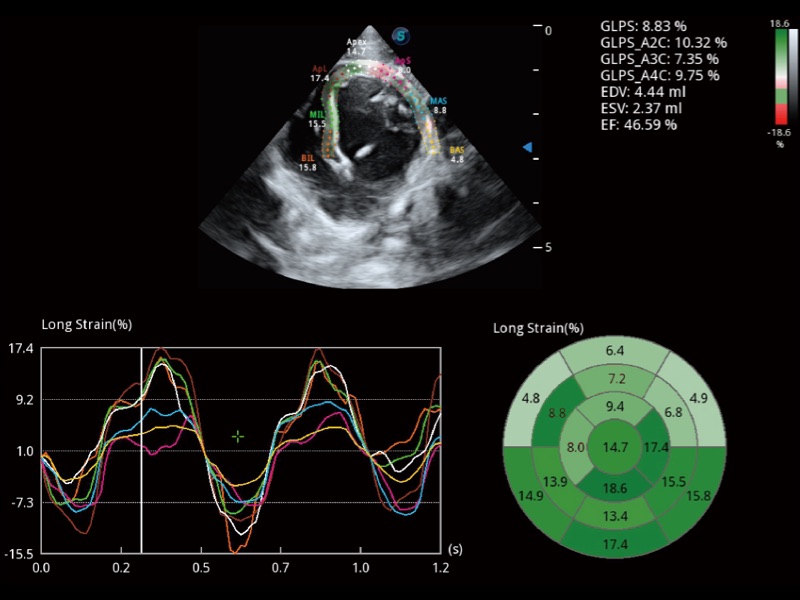

能夠基于左心室壁追蹤和辛普森法,自動(dòng)計(jì)算射血分?jǐn)?shù),支持多個(gè)可移動(dòng)點(diǎn)描跡,與手動(dòng)測(cè)量相比,極大節(jié)省了動(dòng)物醫(yī)生的時(shí)間和精力。

具備多種協(xié)議可選,同時(shí)支持17階段劃分法和專業(yè)的SE報(bào)告。